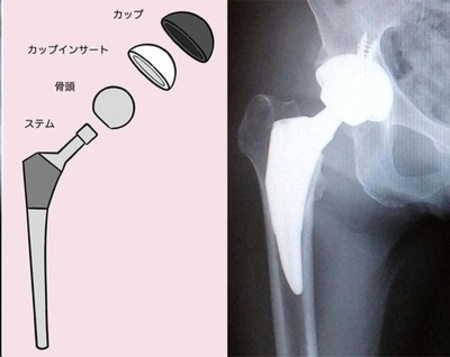

人工股関節置換術とは、簡単にいえば、損傷している股関節を人工股関節(インプラント)に置き換える手術のこと。減量を目的とした生活指導や、筋力を高める運動療法を行ってもあまり効果がみられず、症状が進行している場合は人工股関節置換術を行うことになります。